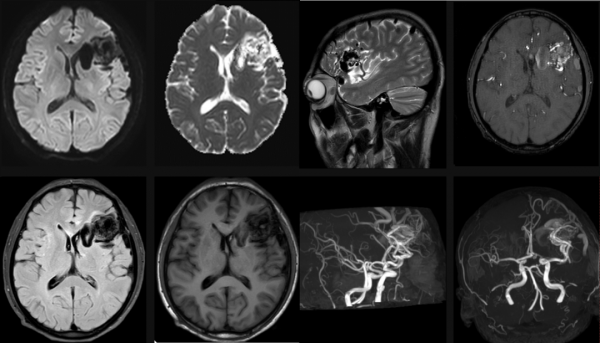

腦動靜脈畸形影像學特徵